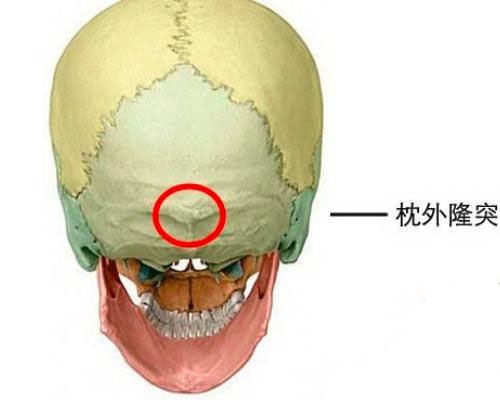

枕骨